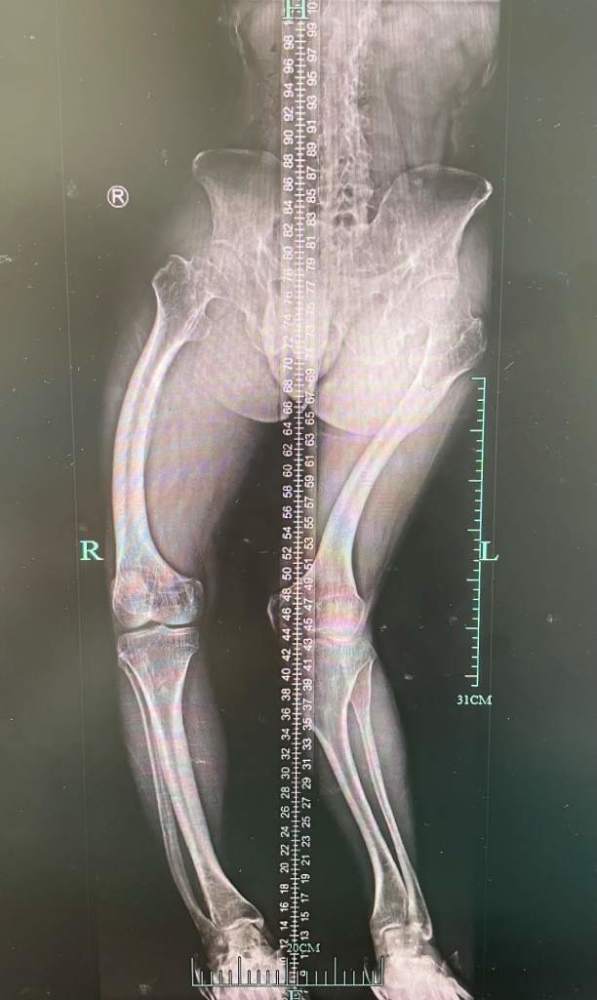

父母连忙带李勇武去医院。经过检查,医生告诉他们,孩子得了“佝偻病”,需要补充维生素D。一家人按照医嘱,每天按时补充维生素D,然而,随着年纪的增长,李勇武的情况却越来越糟糕:脊柱侧弯、膝外翻(X型腿),最让人发愁的是,个子就怎么也长不高了,到了成年,李勇武的身高就固定在了1米48。

看到李勇武的第一眼,黄佼医生就知道这不是一个普通的病例。黄佼医生详细复盘了李勇武发病的全过程,并为他拍片检查。X光片下,只见李勇武全身的骨头都像是一根根弯弯曲曲的面条,严重变形。生化检查发现,他还有低钙血症。